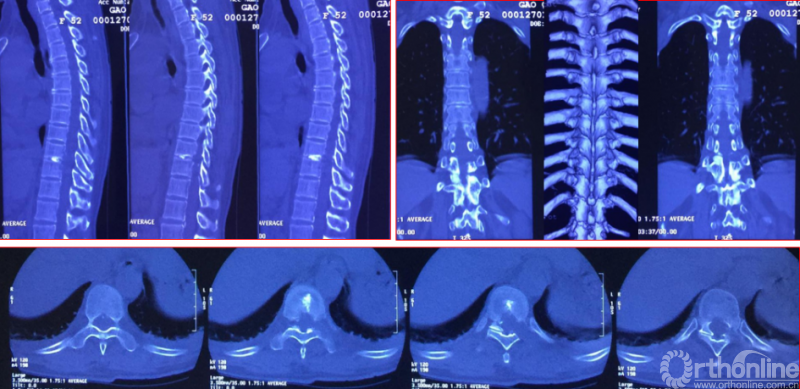

术前资料

手术资料